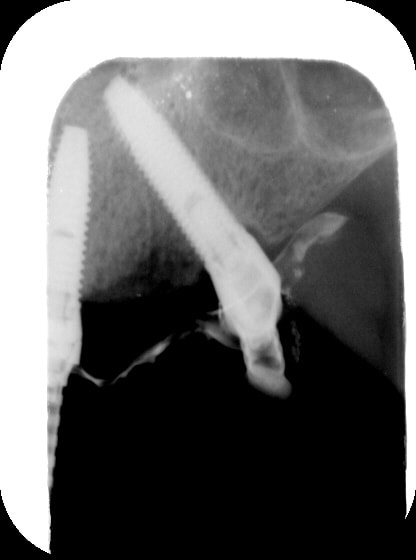

carole

12/09/2006 à 21h55

l' implant en 25 aurait pu etre un peu plus distalé....mais plus court...

je vous montre le bas ;) oups!

(rrrhhh....les radio, dans ces secteurs là aplatissent tout, on dirait des implants presque parallèles... rrhhhh...)

Gin1 vfjd6v - Eugenol

Gin2 lzgl9h - Eugenol

Gin3 zmirus - Eugenol